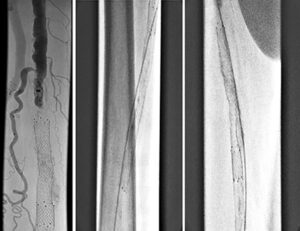

Figure 7. (left) PTA the RCFA, (right) Post PTA recoil

Figure 8. Post-stenting angiogram with double-barrel technique

We gained left femoral artery access with up-and-over technique sheath advance to the right external iliac artery. As expected, we failed to cross the right CFA occluded stent to the jailed right profunda. Ultrasound access was obtained in the right profunda femoral artery in a retrograde fashion. We probed the chronic total occlusion of the ostial segment of the right profunda and the CFA in retrograde fashion, but we could not get into the true lumen of the right external iliac. We then used the IVUS guided crossing device, “Pioneer,” and successfully crossed the occlusion of the right common femoral artery. The entire crossing passage was outside the existing occluded CFA stent and inside the wall of the CFA. The lesion was pre-dilated with a 5×20 mm PTA balloon and then a 6×40 mm PTA balloon. Despite the good release of the lesion at 10 atm, there was severe recoil post dilation of 80% residual stenosis. We inserted a 7×80 mm Zilver PTX DES stent into the right common femoral artery, followed by a balloon expandable short stent at the iliofemoral junction for persistent recoil.

The completion angiogram showed excellent results, with the initial 100% chronic total occlusion of the common femoral artery and profunda femoral vessels reduced to under 30%, and the terminal right external iliac 60% reduced to less than 30%. The entire new stent was deployed in double-barrel fashion alongside the occluded R CFA old stent.  The patient healed her nonhealing right AKA stump wound within three months post intervention. Eighteen months later, recurrent vague stump pain with suboptimal arterial duplex US led to another angiogram (Figure 8) that confirmed continued patency.